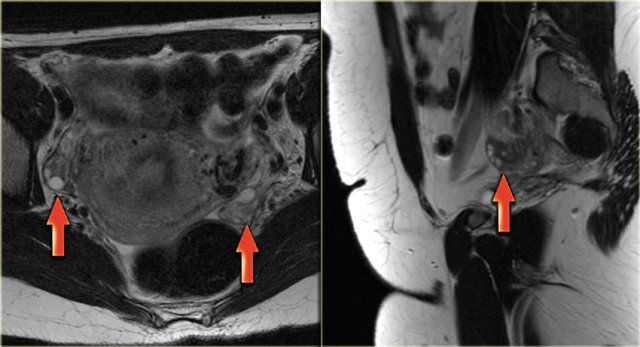

On ultrasound both ovaries are markedly enlarged and contain cystic components with intracystic solid components (arrows).

The complex solid-cystic lesions, in addition to being bilateral, are suspicious for a cystic ovarian neoplasm and warrant further evaluation.

Again, the role of imaging is to confirm a lesion is present and to decide that this is not a lesion that can be classified as definitely benign nor a lesion that can be safely followed-up: action is required.

CT of the same patient confirms large bilateral complex solid-cystic lesions, bulging into the abdomen.

The purpose of the CT is not to confirm what was already known from the ultrasound, but to stage disease.

On the basis of CT (or of MRI) it is not possible to determine the histologic type of the tumor.

This is not relevant. This patient will undergo surgery.

For this patient the relevant findings are on the image on the left.

There is a peritoneal implant.

The tumor was resected and pathology showed this was an endometrioid ovarian carcinoma.